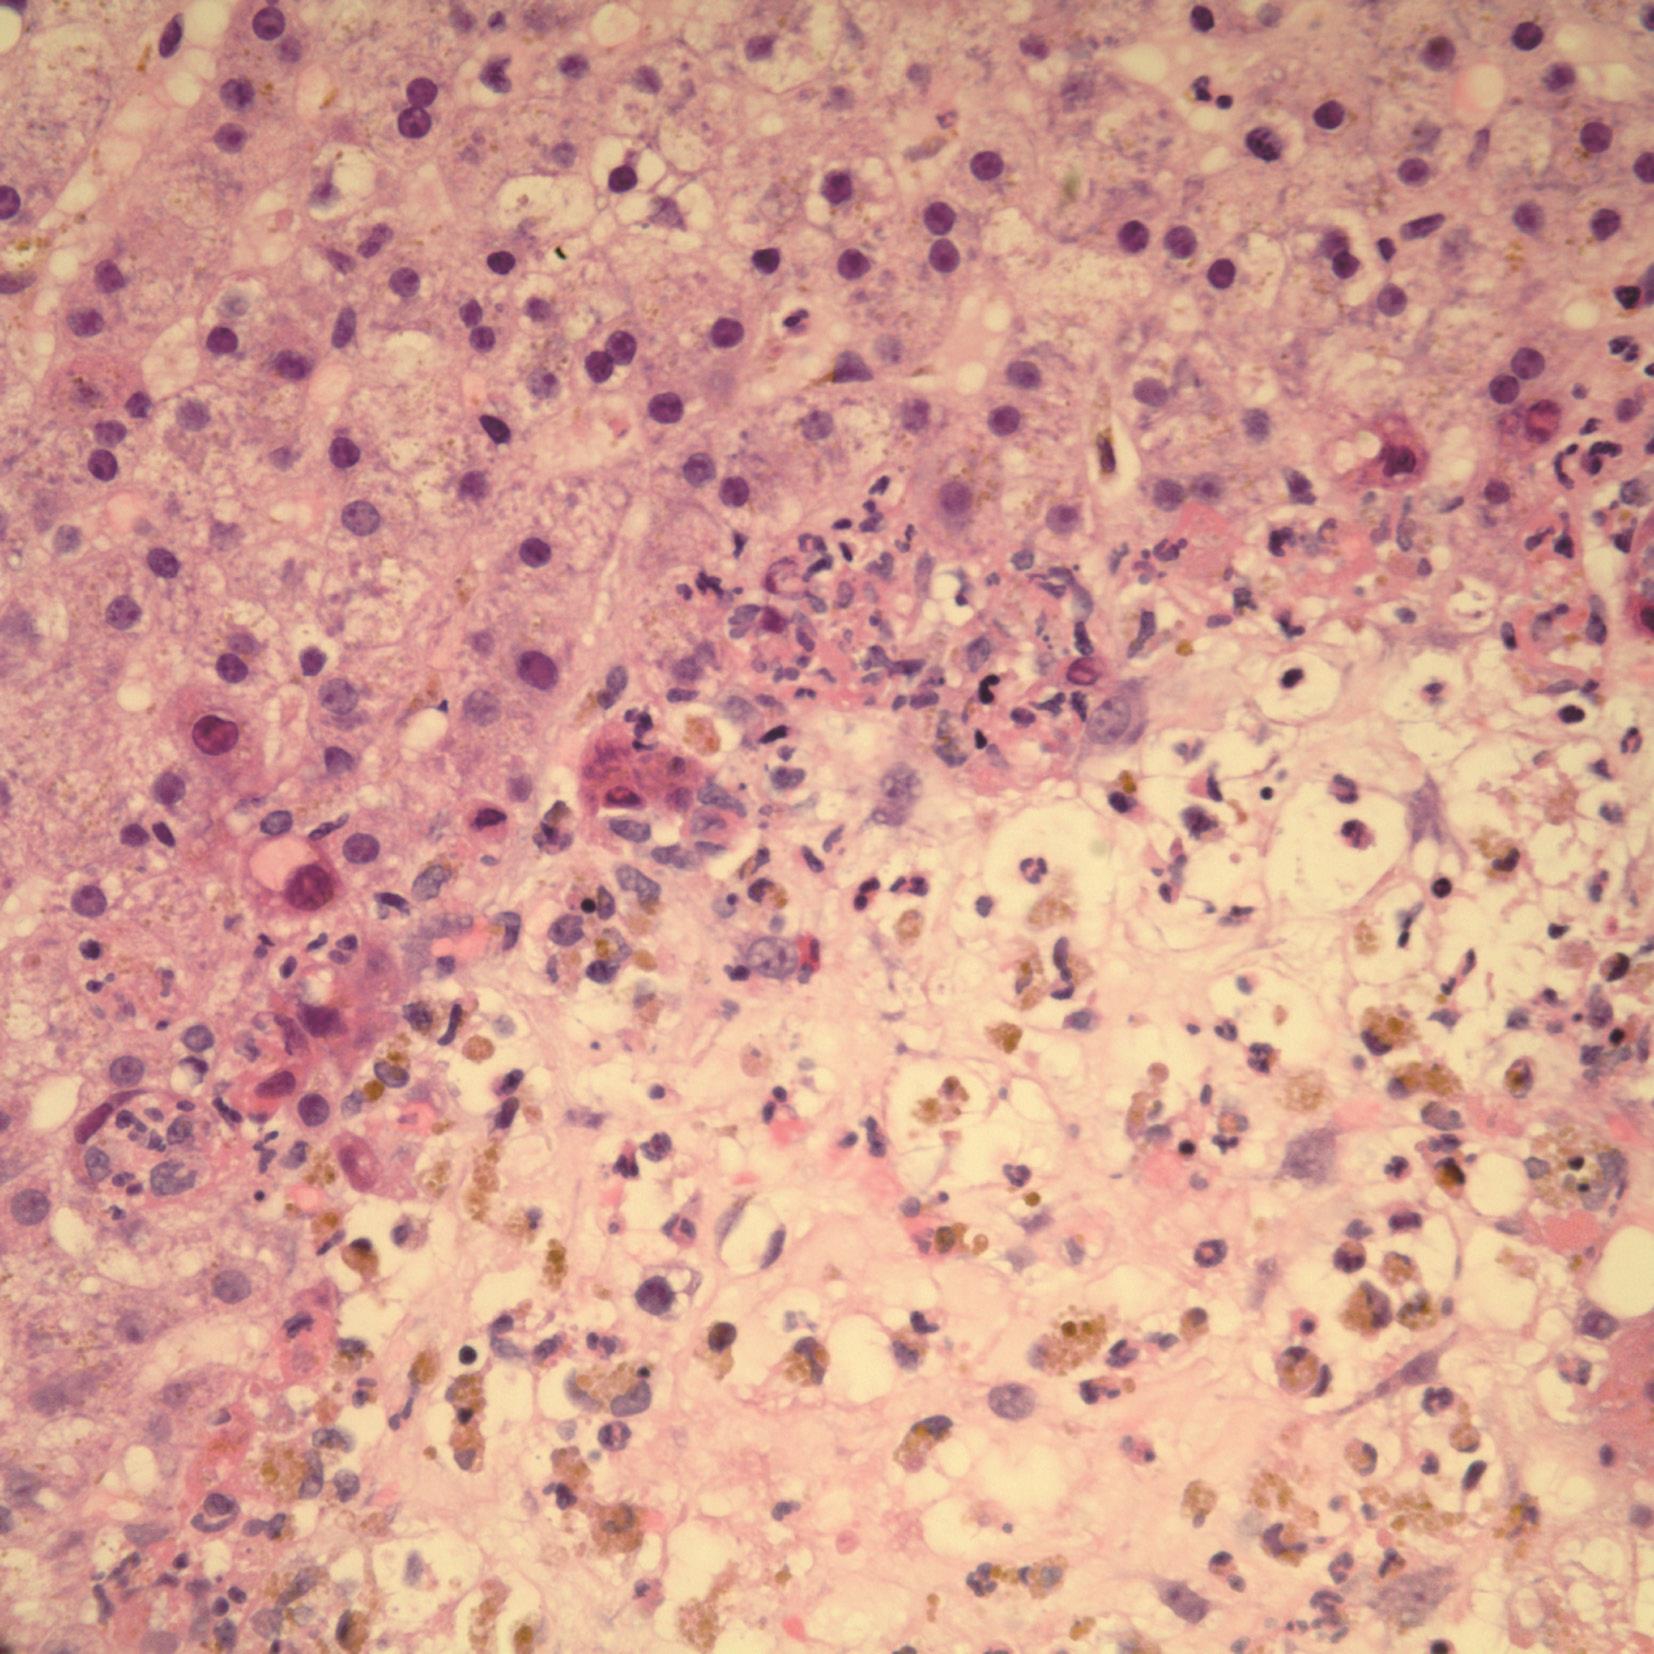

腺病毒肝炎常见于免疫缺陷的儿童或成人,如HIV患者,造血系统恶性肿瘤或移植后患者。病理改变主要表现为广泛的肝细胞坏死和轻微的炎症反应,肝细胞内易查见病毒包涵体(图4-18-3)。病毒包涵体位于肝细胞核内,圆形、嗜碱性、淡染。此型病毒常引起严重的肝炎,并导致肝衰竭,预后差。腺病毒免疫组化染色(图4-18-4)和外周血病毒DNA定量可证实病毒感染。

图4-18-3 腺病毒肝炎